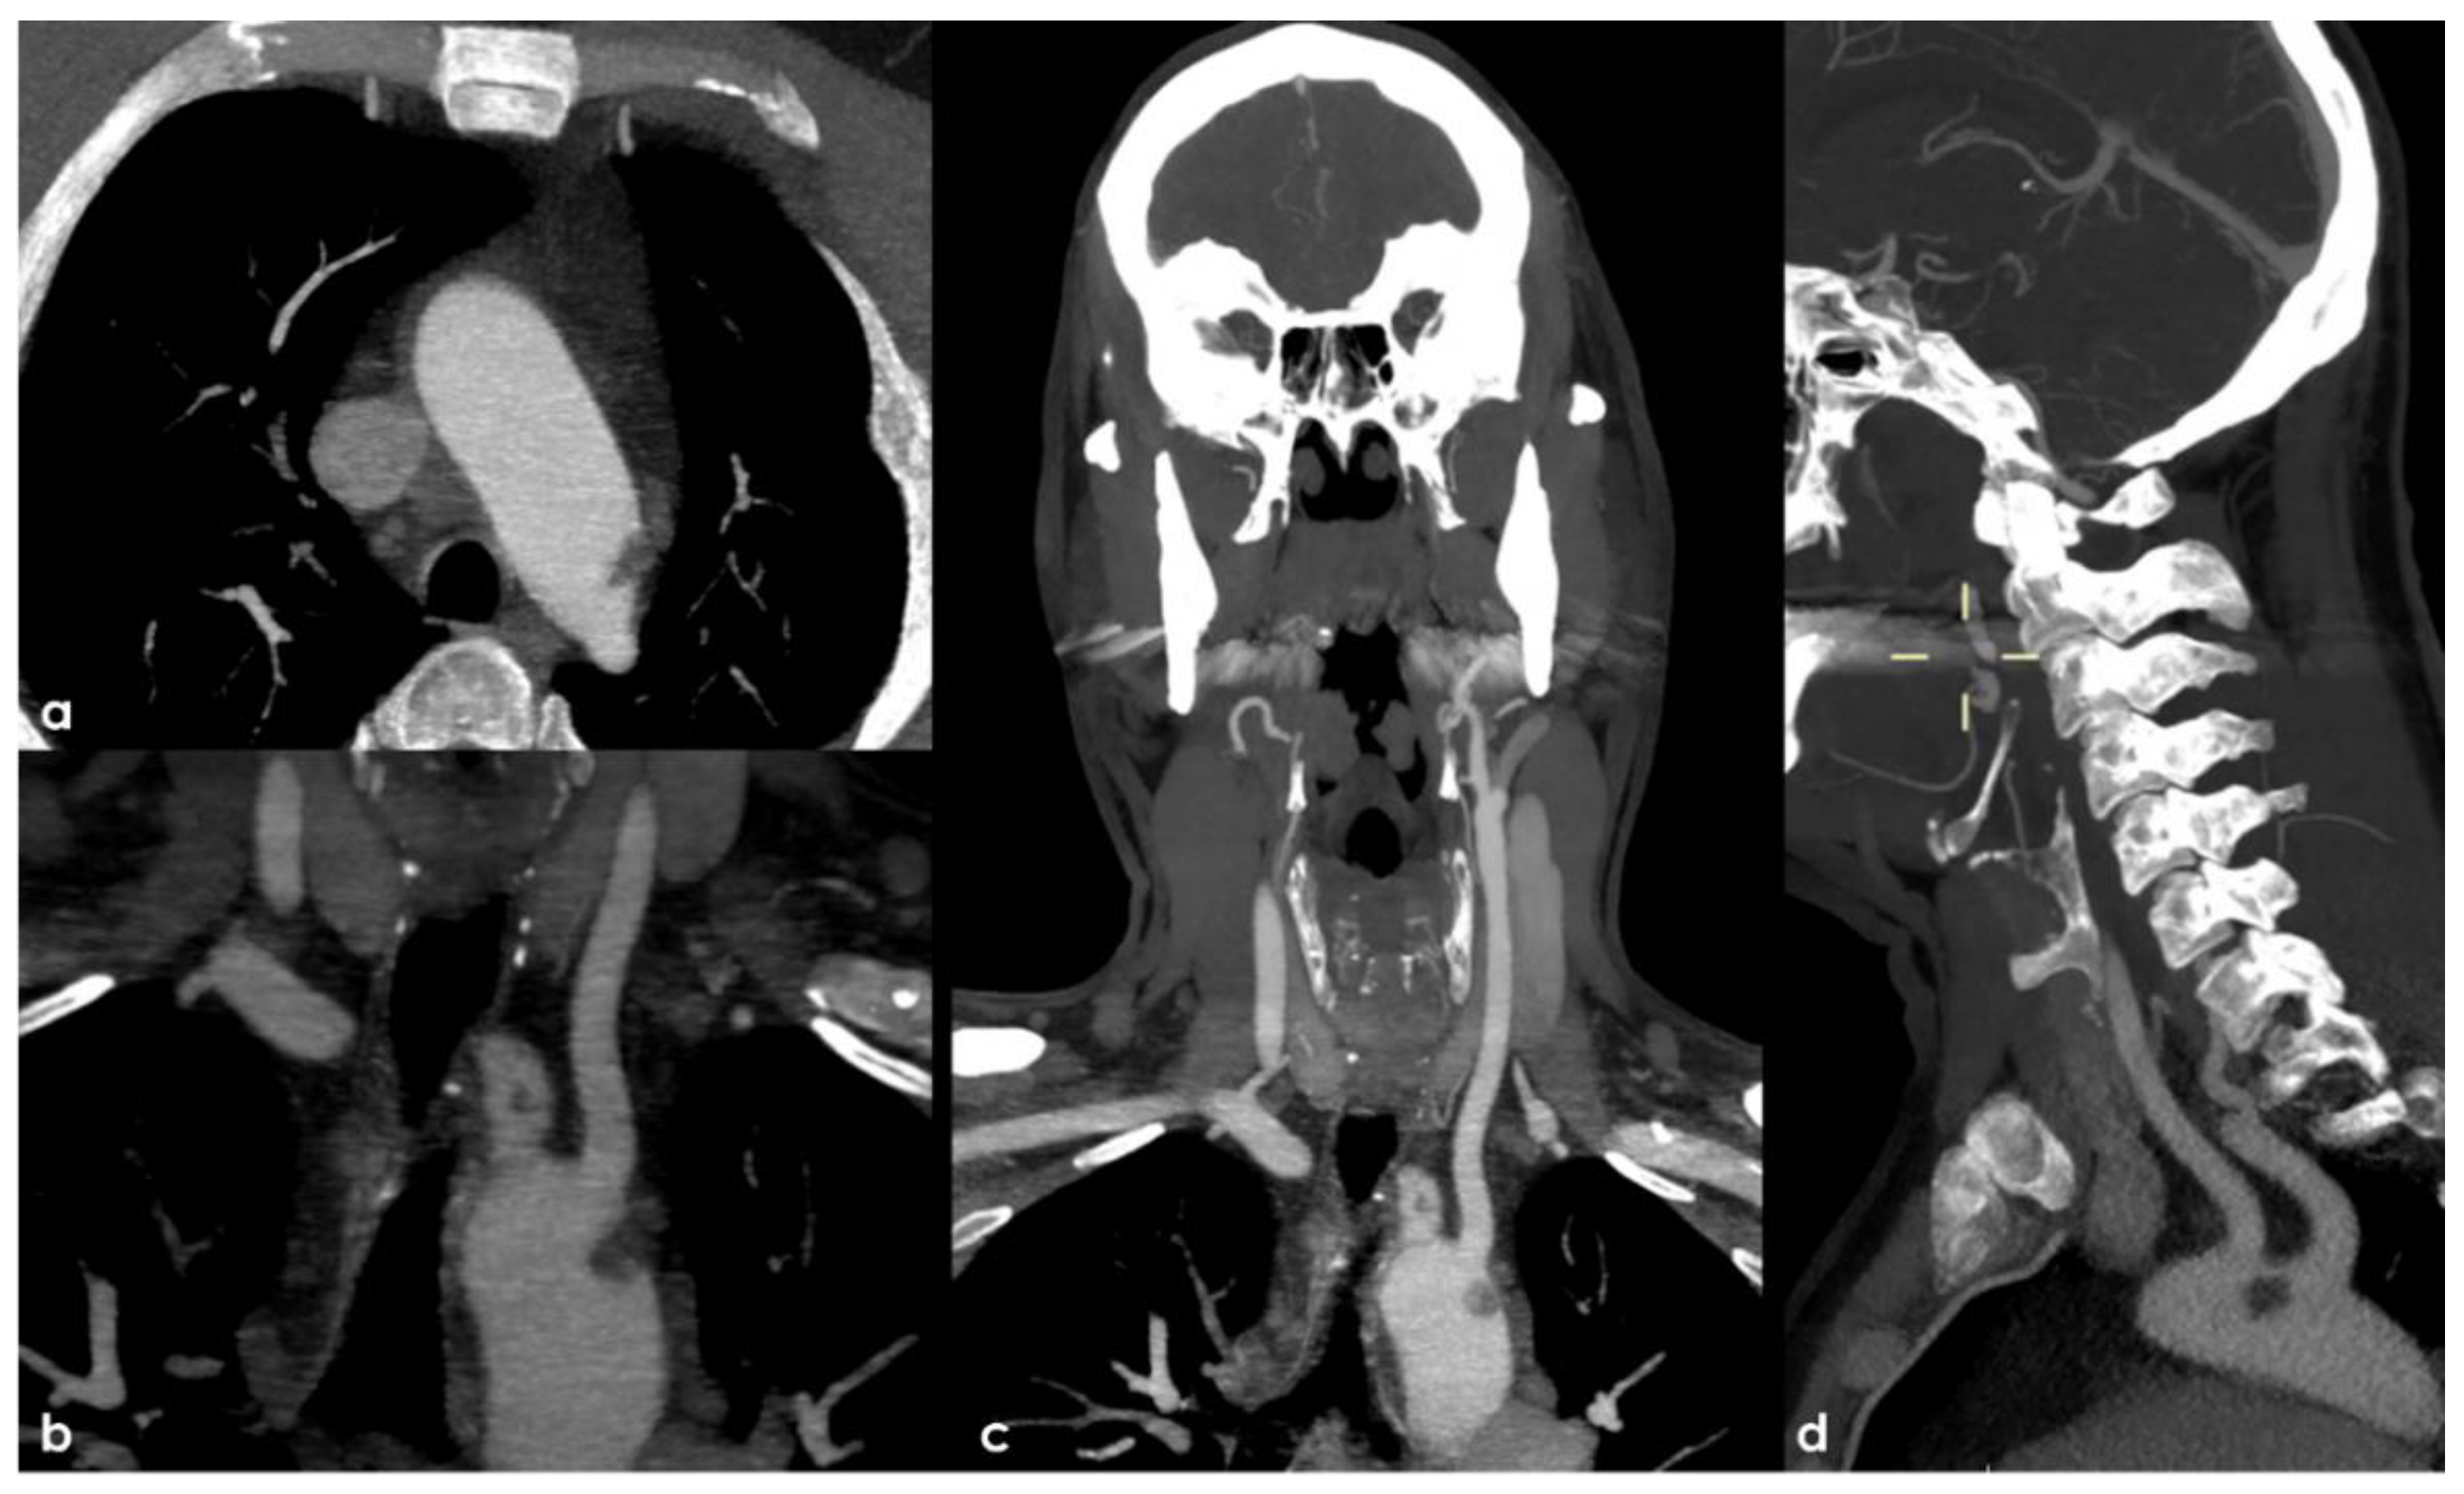

Therefore, an arch-to-vertex CT-angiography (CTA) was performed, and it revealed the following:

• A rounded hypodense lesion partially adherent to the aortic arch wall and partially floating within the lumen of the aortic arch, in the segment between the origin of the left common carotid artery (CCA) and the left subclavian artery (SA);

• A similar smaller hypodense rounded structure partially adherent to the posterior wall of the brachiocephalic artery (BCA);

• A progressive reduction in intensity of contrast filling of the right vertebral artery (VA) starting from the V2–V3 transition, leading to a complete occlusion in the V4 segment;

• A lack of contrast filling of the right lateral dural venous system involving transverse sinus (TS) and sigmoid sinus (SS) and also reaching the jugular bulb and the proximal extracranial segment of the right internal jugular vein (IJV).

The intraluminal arterial hypodensities described in (a,b) (Figure 2) are suggestive for intra-arterial partially floating thrombi with V4 VA occlusion (c) (Figure 3), with a presumed mechanism of artery-to artery embolism. Conversely, the filling defect on the intracranial venous compartment (right TS, SS and IJV) (d) (Figure 4) is highly suggestive of cerebral venous thrombosis (CVT).

Figure 2. Arch-to-vertex CTA. The main findings are illustrated in the pictures from a to d: (a) Axial source slice at the aortic arch level with an irregularly rounded hypodense lesion adherent to the posterior–superior wall of the aorta and partially floating into the lumen; (b) Maximum Intensity Projection (MIP) reconstruction on a coronal plane at the level of the hypodensity seen in a and showing the spatial relationship with the left CCA origin (magnified picture). A similar smaller rounded hypodensity, apparently floating into the BCA lumen is also evident; (c) The same MIP coronal plane as in b with a minor magnification, allowing to better appreciate the final potential locations of artery-to-artery embolism from the above signaled thrombotic formations; (d) MIP reconstruction in a sagittal plane showing the site of the aortic arch thrombus between left CCA and left SA.